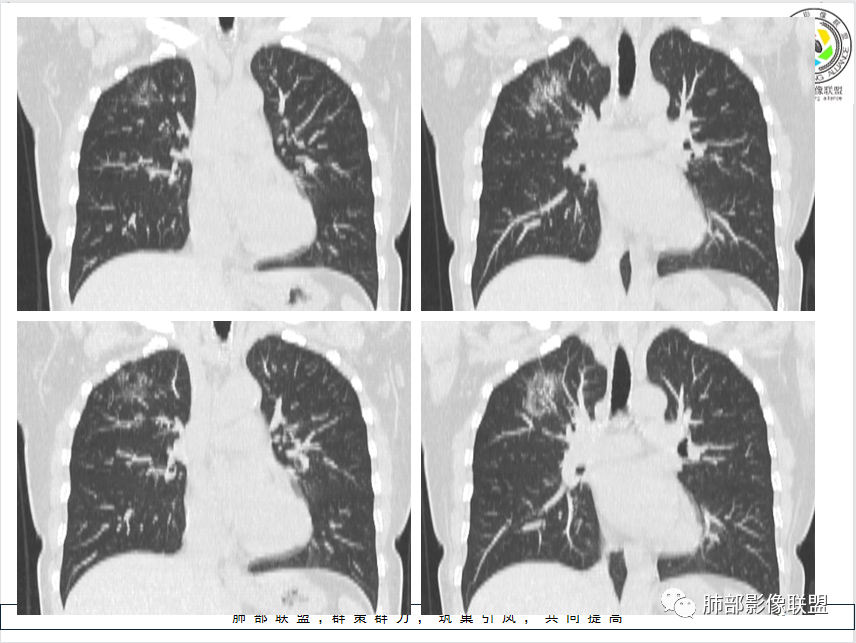

影像特点:右肺上叶混合磨玻璃影,边界清晰,结构松散,内有多结节堆积及支气管扩张影,可见小叶间隔增厚,并局部增厚的小叶间隔上亦存在微结节,胸膜侧可见纤细索条,病灶周围可见多发微结节影。

总体分析:从病灶分布来看符合结核的好发位置,影像表现也符合结核的多态性,且出现卫星灶。由于有边界清晰的GGO,需要鉴别腺癌,虽然此病例有边界清晰的GGO,但是它的GGO的边缘有结节感,呈多结节堆积,而腺癌的GGO缺乏这种“多结节堆积感”,另外,此病例也没有发现腺癌的胸膜凹陷征、毛刺征及月牙铲等。

间质性肺结核是结核的一种特殊影像学表现,为继发性肺结核,影像学表现与常见的继发性肺结核有所不同,有一定的特征性。

1、年轻人多见,一般提示免疫力可能有下降。 2、好发部位与其它结核类似,上叶及下叶背段为主。 3、烟花征,反晕征,环呈结节状,可以伴随空洞,树芽征,结节灶,胸水。(反晕征:一般周围实性环形高密度影,中央丛密度低;一般环超过圆的3/4,结核的环主要是小叶核心结节组成,类似于多发树芽征聚集,边缘结节感。中央的晕:可以是腺泡结节,树芽征,细网状,磨玻璃影,很少正常,主要成分是小叶内间质增厚、小叶核心结节、肺泡内病变。)其实也体现了结核的多灶性、多态性特点。

4、其实不一定完全表现为反晕征,还有比较密集的烟花,聚集成团,与反晕征同在。